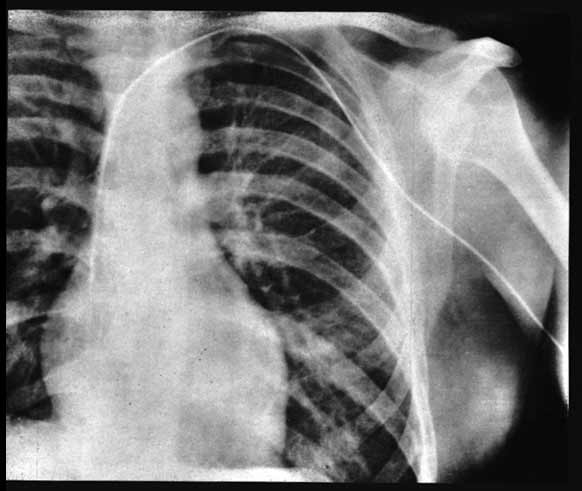

X-ray of Werner Forssmann

In 1929 he performed the 1st human cardiac catheterization, ignoring the strong orders of the department head. As at the time, this kind of procedure was surely believed to be fatal, he decided to do the procedure on himself. He anesthetised his elbow area and introduced a urinary catheter into a vein in the elbow area, which under X ray guidance, he passed up to his right ventricular cavity. He faced strong disciplinary measure for his experimentation. His negative reputation and image, with his seniors, forced him to quit Cardiology and instead take up Urology.